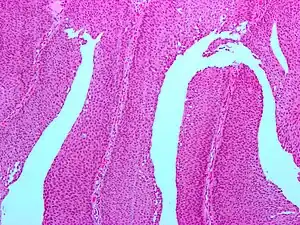

| Micrograph of a PUNLMP. Intermediate magnification. H&E stain. | |

Histologically, they have a papillary architecture with slender fibro vascular cores and rare basal mitoses. The papillae rarely fuse and uncommonly branch. Cytologically, they have uniform nuclear enlargement.